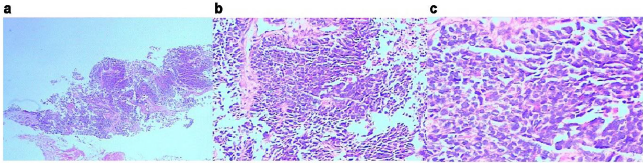

Figure 2: Pathological biopsy of the left chest wall.

a. HE, x2.

b. HE, x200.

c. HE, x400.

The cell layers were clustered and nested, and organ-like structures were seen. The cells were small with less cytoplasm, unclear nucleoli, partial vacuoles in the nucleus and chromatin. Karyokinesis was observed with local coagulation necrosis.